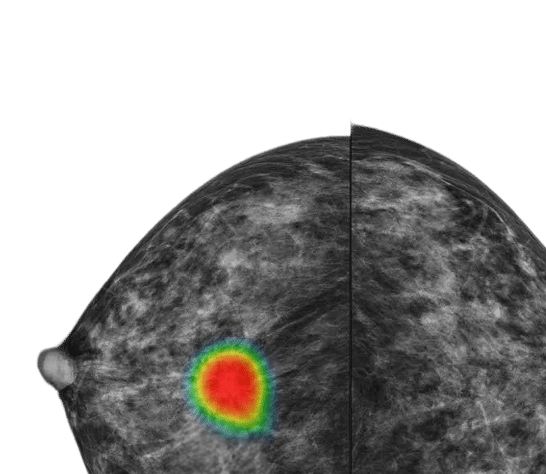

In a retrospective analysis, Lunit INSIGHT MMG correctly identified suspicious findings in a mammogram from 2020 that was originally overlooked. The patient was not diagnosed until 2022—highlighting the potential of AI mammogram reading tools to support earlier diagnosis.

Up to 40% of breast cancer cases* can be diagnosed earlier with AI support.

*Nanaa et al. Accuracy of an Artificial Intelligence System for Interval Breast Cancer Detection at Screening Mammography. Radiology 2024.